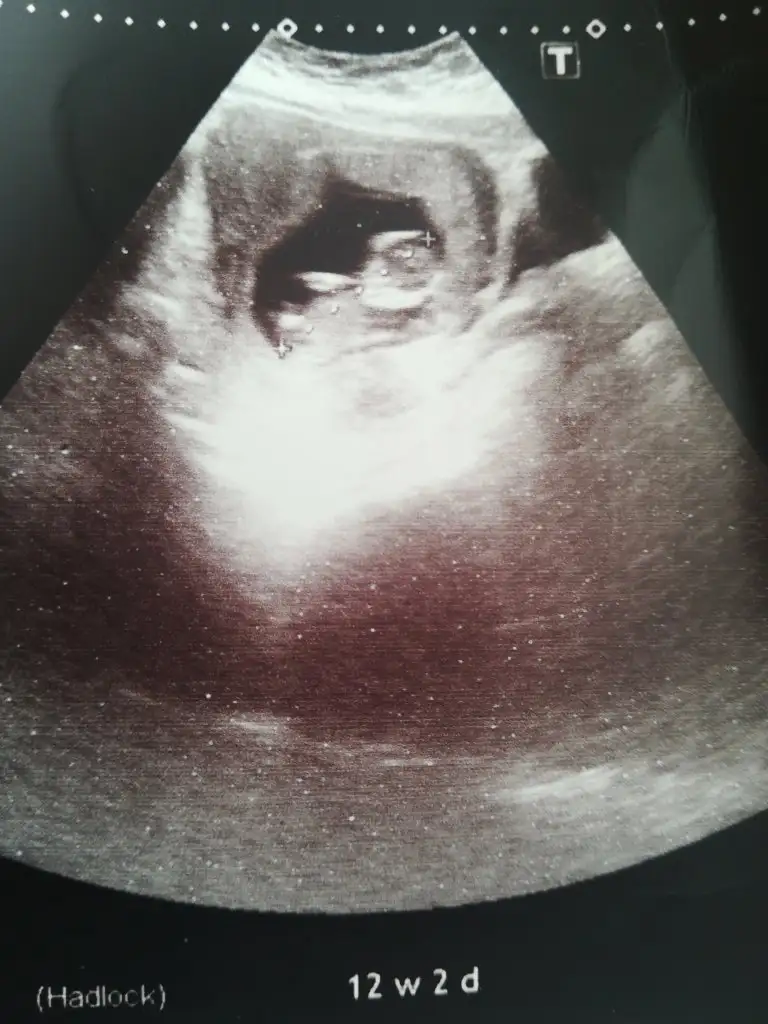

Başka usg varmı net degil erkek gibi geldi bana eminde olamadım12+2 ama yüzü donukmus tahmin varmi